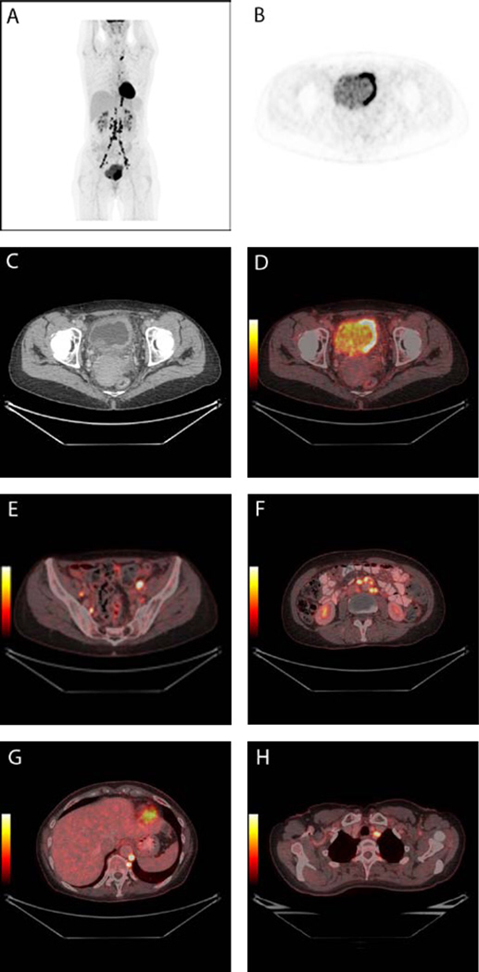

Le TEP-scan

La réalisation d’un TEP-scan FDG est indiquée dans le cadre du bilan d’extension de la tumeur de vessie.

Il va permettre d’apprécier la présence d’une dissémination ganglionnaire ou viscérale de la tumeur et de permettre de préciser les indications.

Un patient de 56 ans atteint d’un cancer infiltrant de la vessie recemment diagnostiqué a subi une TEP/CT 18F-FDG à des fins de stadification. L’image TEP montre la tumeur dans la vessie ainsi que de multiples métastases lymphatiques (2A). La tumeur est visible sur le côté gauche de la vessie sur l’image axiale TEP (2B), l’image CT (2C) et l’image fusionnée TEP/TDM (2D). Les métastases mul-tiples sont observées dans les ganglions lymphatiques situés des deux côtés de la région pelvienne (2E), dans les ganglions lymphatiques retro-peritoneaux (2F), dans les ganglions lymphatiques rétrocruraux et dans un ganglion lymphatique du côté gauche de la trachée (2G).

Habituellement, dans le cadre du bilan d’extension d’une tumeur de vessie, l’uroscanner et la réalisation d’un TEP-scan FDG sont suffisants. D’autres examens, comme la scintigraphie osseuse, l’urographie intra veineuse ou la radiographie pulmonaire standard, de ce fait sont devenus inutiles..